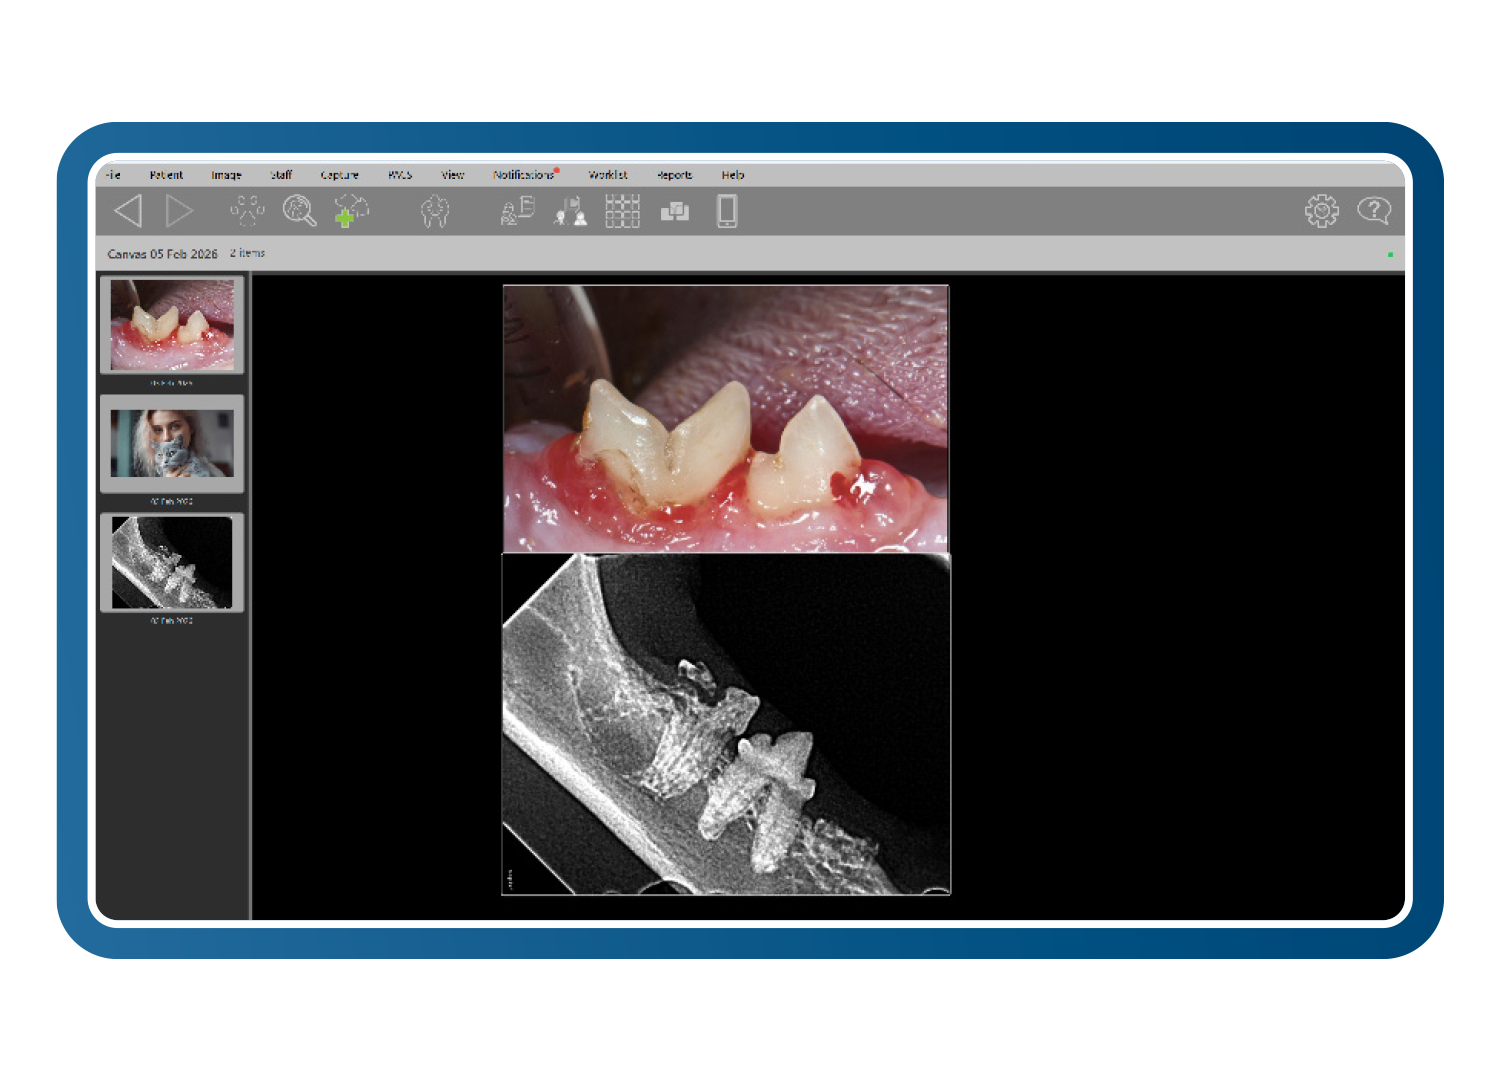

Imágenes conectadas con el cliente

Vincule de forma segura teléfonos y tabletas a los historiales individuales de los pacientes, permitiendo que el personal o los propietarios de las mascotas carguen imágenes directamente en el expediente clínico. Estas imágenes facilitan consultas más claras, mejoran la comprensión del cliente y aumentan de manera constante la aceptación de tratamientos dentales de aproximadamente un 10 % a más del 60 %.

Diseños intuitivos de boca completa y formato libre

Cree conjuntos de imágenes diagnósticas claros y completos utilizando diseños intuitivos de boca completa y formato libre para múltiples especies. Las imágenes se colocan automáticamente en la posición correcta, con una edición sencilla mediante arrastrar y soltar. Combine radiografías y fotografías para presentar una historia diagnóstica coherente y fácil de entender.